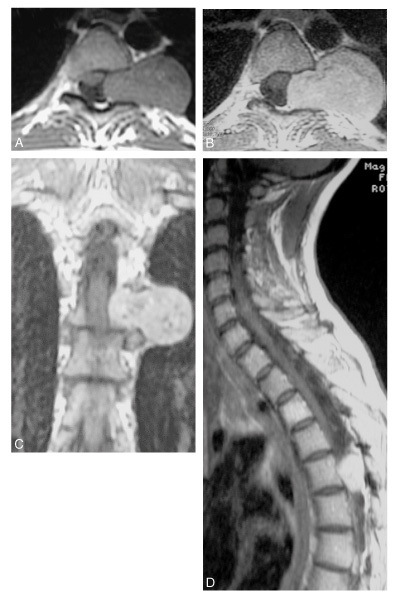

Diagnostic?

Neurinome en sablier T5 -T6 gauche

Quel diagnostic?

myélopathie cervicarthrosique C4-C5 avec hypersignal médullaire